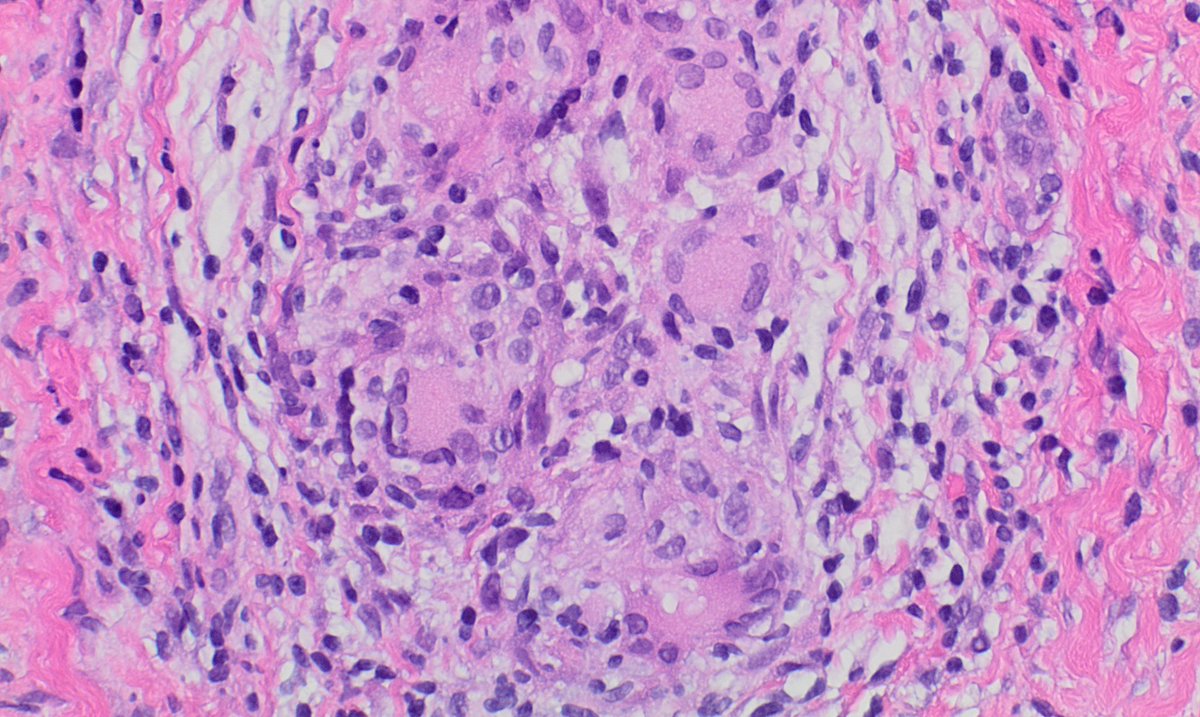

Hi all! Common #pulmpath scenario: adult W, smoker, 5 cm lung mass. No known Hx & no lesions elsewhere.❓for #pathologists: is IHC needed here or is this c/w lung primary based on clinical setting & histology? (obvious bait, but good real-life scenario to discuss) #natpathpuzzler

Lung lesion. What stains will you request #lungpath @ac_pathgal @raghupillappa @HansiniMD @SanicaBheleMD @NupursharmaMD @Sujata_path @JayaVen @SusanKarki777 @AlainCagaanan @Ramavid15 @Drsandeep89 @DonthiDeepak @DrNidhiKataria @DrGeeONE @kkuanMD @TheKarenPinto @ALBoothMD @Debdasmd